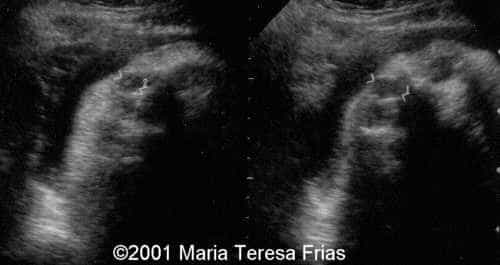

This is a case of Dacryocystocele.